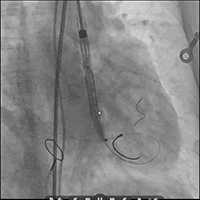

● 更换新瓣膜跨瓣后,猪尾难以送至无冠窦底,故行造影定位窦底。

隐约可见“无冠窦”后部更深窦底,位于“无冠窦”下约6mm,参考该位置后进行0位定位,无起搏逐步释放至工作位,瓣膜无明显位移表现,瓣膜形态压缩良好,造影评估无反流。准备释放瓣膜。

无张力释放,脱钩后瓣膜略微下滑,约位移瓣环下4~5mm位置,瓣膜整体形态良好,造影评估无可见反流。